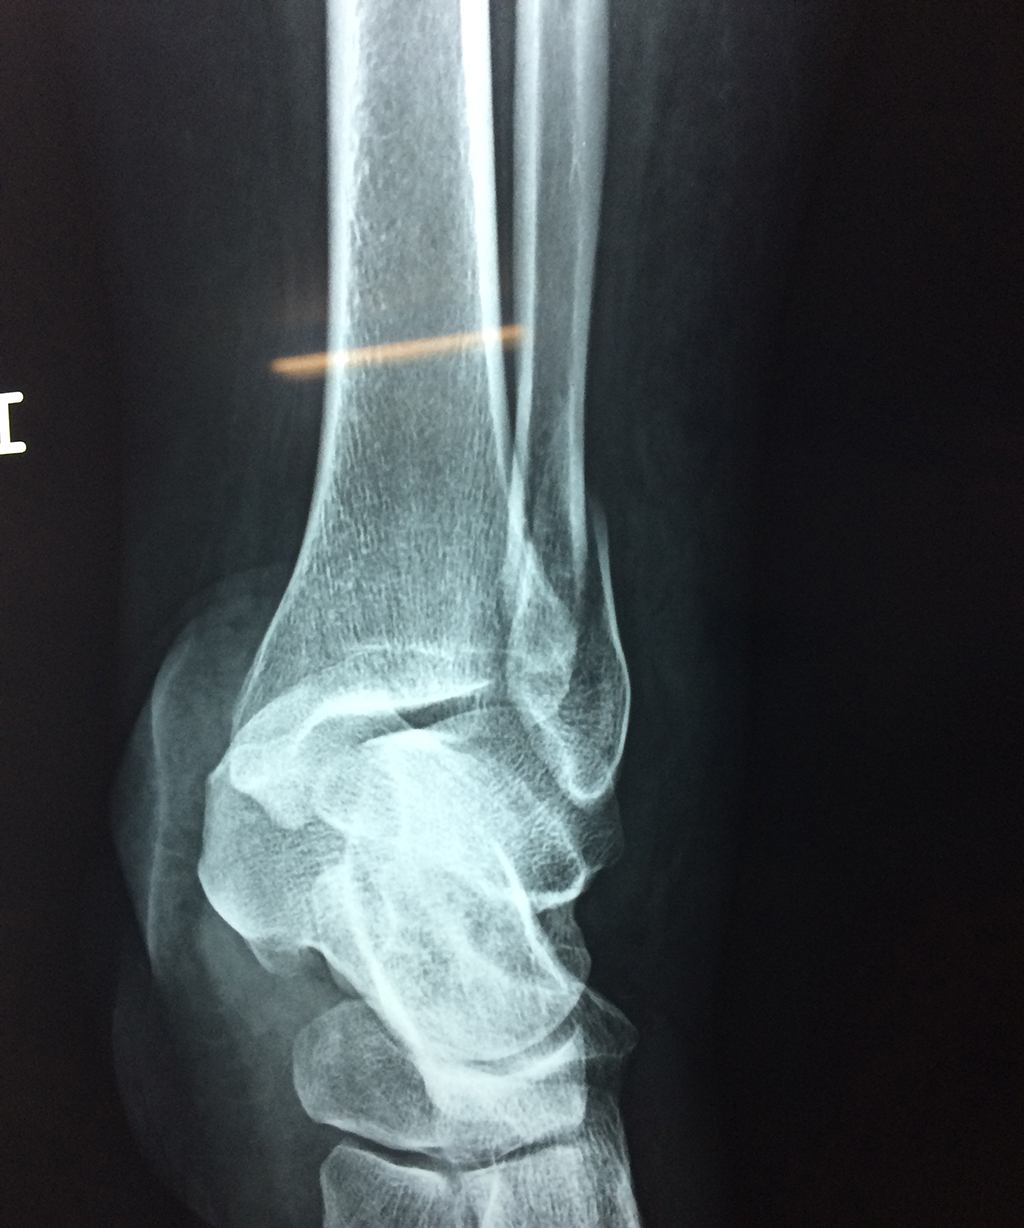

Una fractura de tobillo es la rotura de uno o más de los huesos del tobillo. Estas fracturas pueden ser:

- Parciales (el hueso está sólo parcialmente fisurado, no del todo).

- Completas (el hueso está perforado y está en 2 partes).

- Producirse en uno o ambos lados del tobillo.

Algunas fracturas de tobillo pueden requerir cirugía si:

- Los extremos de los huesos están desalineados entre sí (desplazados).

- La fractura se extiende hasta la articulación del tobillo (fractura intra-articular).

Cuando se necesita cirugía, es probable que esta implique el uso de clavijas de metal, tornillos o placas para sostener los huesos en su lugar mientras la fractura se consolida. Los elementos de soporte pueden ser temporales o permanentes.